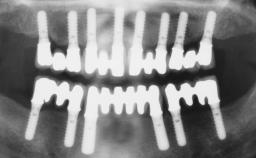

Immediate Implant - Immediate Temporary: Guided Surgery in the Esthetic Zone

In this video Dr. Nikos Mattheos demonstrates the full diagnostic, planning and treatment sequence of an immediate implant with an immediate prefabricated provisional restoration in the esthetic zone. A 28 years old female patient presents with discoloration and increasing mobility of tooth 11. Advanced stage of external resorption is diagnosed. Patient's high esthetic demands combined with intact gingival architecture and periodontal health makes her a good candidate for immediate placement and restoration to preserve the gingival contour. Surgical and restorative treatment is planned with digital workflow based on data from CBCT and intraoral scan. An immediate temporary crown is manufactured for placement at the day of the surgery. Flapless extraction is performed, and the implant placed with guided surgery. Consequently, the buccal gap of the socket is augmented with Xenograft, while the soft tissue space maintained with a collagen plug. Finally, a provisional crown is immediately placed on the implant with a titanium temporary abutment and an emax prefabricated crown.

Timing of placement Immediate Placement (extraction sockets) (Type I)

Available apical bone to achieve primary stability Sufficient height ( ≥ 4 mm) and width (> 2 mm around apex of planned implant)

Socket walls Intact